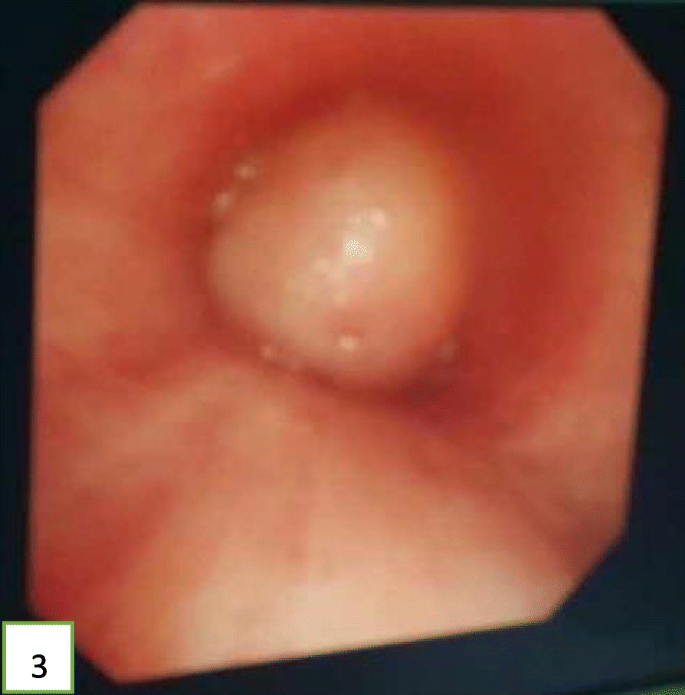

A 52-year-old Chinese man presented at the clinic reporting a mild cough with yellow color sputum and exertional dyspnea for 2 weeks. He denied any fever, chest pain, night sweats, or weight loss. He was a heavy smoker (45 pack-years) and had a history of a splenectomy for abdominal injury 23 years ago. After a failed 3 day-course of antibiotic treatment at the clinic, he was referred to our hospital for further examination and treatment. Upon physical examination, the body mass index (BMI) was 17.97, SpO2 was 98% when breathing ambient air, the respiratory rate was 20/min, and the blood pressure was 119/77 mmHg. Chest auscultation demonstrated faint wheezing in left lower lobe. A computed tomography (CT) scan was performed, which revealed two low-density endobronchial masses located in the middle segment of the left main bronchus and the posterior basilar segmental bronchus of the left lower lobe. The neoplasms measured the CT-attenuation value -70HU, −98HU (Figs. 1 and 2) in density with air trapping and atelectasis in the segmental bronchus of the left lower lobe. The complete blood count showed that the white blood cell count increased to 16 * 10^9/L, the platelet count increased to 549 * 10^9/L, whereas other blood cell counts were within the normal range. No abnormalities were observed in liver function, renal function, blood lipids, blood glucose, C-reactive protein, and erythrocyte sedimentation rate. The tumor markers alpha fetoprotein (AFP), carcinoembryonic antigen (CEA), carbohydrate antigen 125 (CA125) and carbohydrate antigen 19–9 (CA19–9) were in the normal range, and no acid-fast bacilli were found in sputum smears. Subsequently, the patient underwent a flexible bronchoscopy, which confirmed an exophytic spherical lesion that caused almost complete occlusion of the middle of the left main bronchus (Fig. 3), however, the cytological diagnosis failed by using bronchoscopic brushing cells.

In view of the above, interventional bronchoscopic management was undertaken to remove the neoplasms. First, we therapeutically resected the neoplasm, of which the base was located in the lateral wall of the left main bronchus using electrosurgical snare under flexible bronchoscope (Fig. 3). Then, the spherical and pink neoplasms were taken out by cryotherapy (Fig. 4). Subsequently, another yellowish dumb-bell neoplasm was found in the superior segment of the left lower lobe (Fig. 5) and the main part of the neoplasm was removed (Figs. 6 and 7) by electrosurgical snare, electrocautery, and cryotherapy. Only the C branch of the superior segment of the left lower lobe could not be completely resected or ablated (Fig. 8) because the neoplasm originated distally. Histopathological examination confirmed that both tissues from the left main bronchus and the superior segment of the left lower lobe were consistent with lipoma (Figs. 9 and 10).